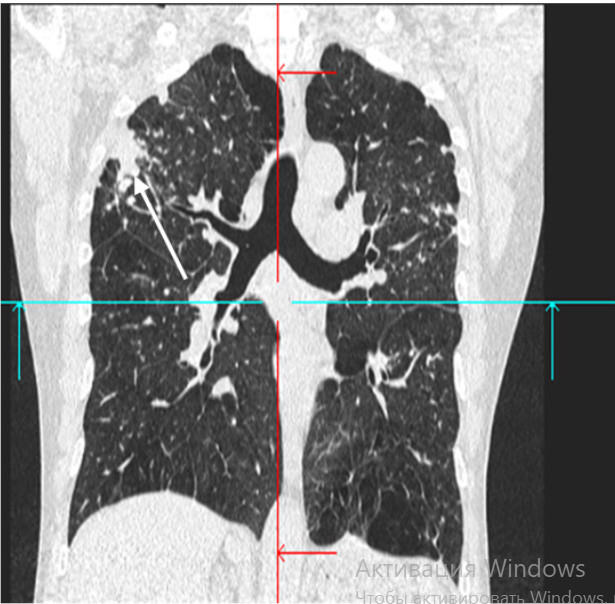

При компьютерной томографии органов грудной клетки выявляются множественные узелковые образования с характерными особенностями: образования имеют чёткие ровные контуры и преимущественно располагаются в периферических отделах лёгочной ткани, часто находясь в непосредственном контакте с плевральными листками. Вокруг основных узелков нередко визуализируются мелкие сателлитные образования. В структуре узелков могут определяться участки распада с формированием полостей, а также зоны кальцификации. Размеры выявленных образований варьируют от мелких очагов до крупных узловых структур. При динамическом наблюдении отмечается стабильность выявленных изменений либо их медленный рост[2].